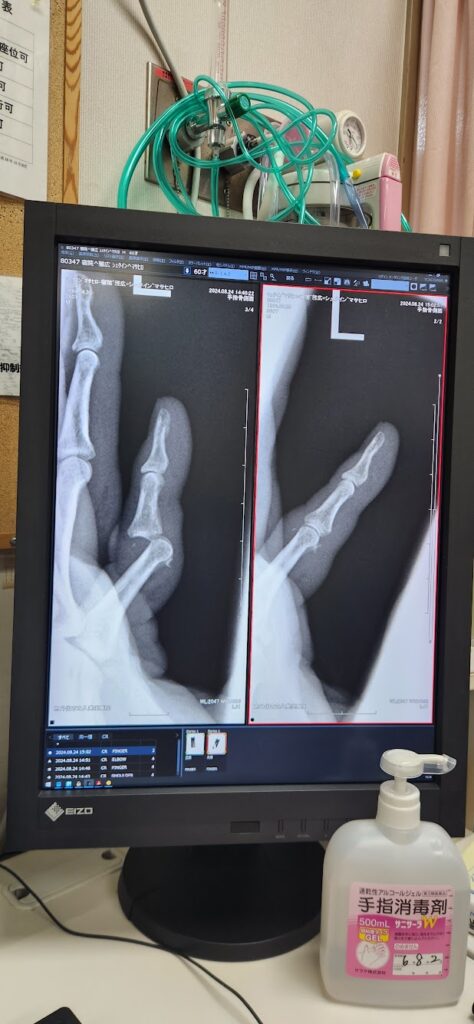

少しだけ剥離骨折も見られ、本当は手術するべきだったのですが、その翌週にはニュージーランドで4か月の勉強が始まる予定